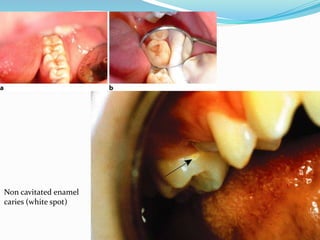

 Visual evidence of caries includes white spot ,cavitation,

or discoloration.

Non cavitated enamel

caries (white spot)